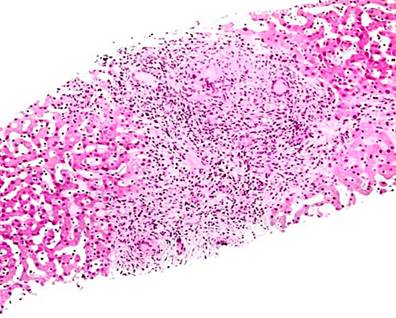

Three greyish-brown elastic fragments with whitish nodules, of which the largest measures 1.6 x 1 x 0.5 cm and the smallest 0.8 x 0.3 cm, were sent to the laboratory. The specimen was fully processed, and histochemical stains (reticulin, periodic acid Schiff [PAS], and Masson’s trichrome) were performed for microscopic evaluation.

In the microscopic evaluation, hepatic tissue with alterations of the standard architecture was seen due to an extensive area of caseation necrosis. Outside, epithelioid cells, Langerhans-type giant cells, and fibrosis were found. In addition, a remnant of hepatocytes with distorted architecture and portal spaces having a fibrous expansion, hydropic degeneration, and sinusoidal congestion was detected. In some areas, there was ductal proliferation. The conclusion of the liver biopsy indicated a granulomatous inflammatory process with caseation necrosis compatible with M. tuberculosis. Figure 5 shows a representation of the histological section. As a result, the pathology department suggested correlating the histopathological findings with the patient’s symptoms.